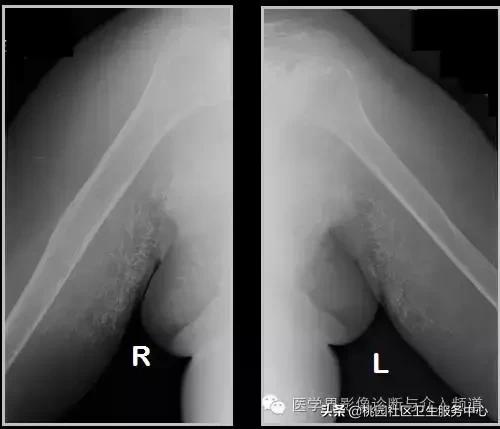

六、肌腱钙化/滑囊炎并钙化

肩关节最常见:肱二头肌长头、肩峰下滑囊钙化,可伴有急性疼痛、肿胀,局部压痛。

大粗隆滑囊炎